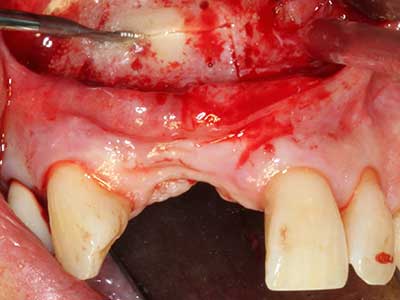

Indication: Periodontal therapy

Marginal periodontal diseases are the main reason for extractions in advanced age. These diseases are primarily caused by bacterial colonization of the gingival pocket, which causes inflammation followed by loss of the periodontium. The formation of subgingival biofilms and concrements is a significant aetiological factor for marginal bone atrophy, so their removal is an important part of the treatment (Drisko 2014, Plessas 2014).

Initial and surgical treatment phases are differentiated in the treatment of marginal periodontitis. In addition to instruction in oral hygiene and motivating patients, both phases should include adequate cleaning of the root surface. In the regenerative setting an open access is generally preferred. The root surface can be cleaned by piezo surgery using special attachments, where instruments with different curvatures are used to reach areas that are difficult to access, such as furcations. The integrated irrigation in the system flushes the detached concrements and bacteria out of the pocket. Specialized systems such as the Piezomed also include application feedback to minimize the ablation of hard dental substance. The greater the pressure on the periodontal attachment the greater the reduction in the amount of ablation.